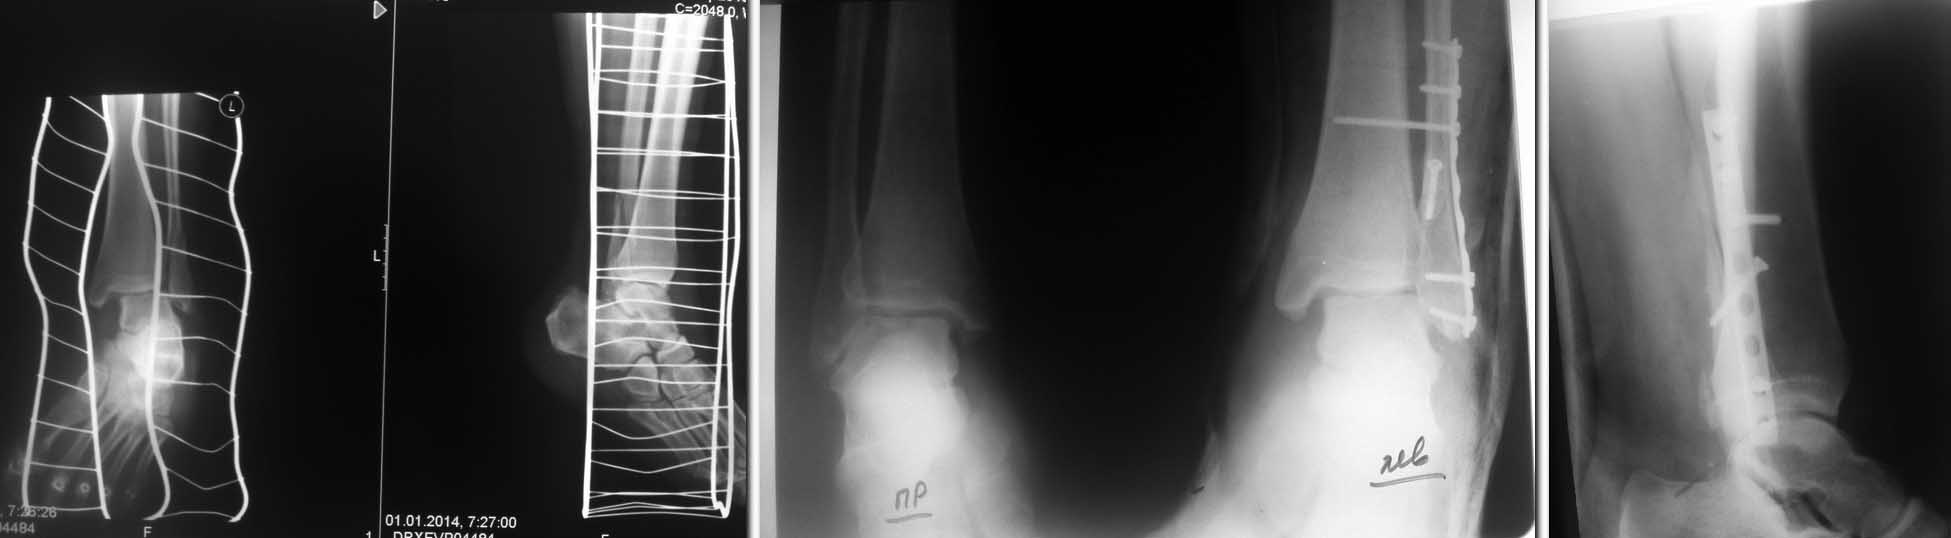

Уважаемые коллеги, на днях прооперирована обычная лодыжка у молодого парня, а именно м/берц кость, перелом 44-B3.1наружная лодыжка открыто репонирована один к одному, ревизирована дельтовидная связка, установлен синдесмозный винт...но все же на контр р-граммах подвывих сохраняется. Вопрос: где ошибка и нужно ли оперировать повторно.

На первичных снимках - разрыв дельты, явное повреждение синдесмоза, жуткий подвывих.

1. Длина м/б не восстановлена;

2. Скорее всего при стягивании обеих берцовых костей (установке позиционного винта), наружная лодыжка не совсем попала в синдесмозную щель (по боковым снимкам, она либо кзади либо ротирована)

3. Ревизию дельты сделали - и что? надо сшивать чрескостно с формированием канала в мед. лодыжке (а после операции на недельки две в гипс в положении варуса)

4. Синдесмозный винт проведен высоковато, лучше всего - у верхнего края синдесмоза (4-5 см проксимальнее сустава)

Не восстановлена длина малоберцовой кости - отсутствует линия десятицентовой монеты на передне-задней п/о рентгенограмме (dime sign). Отсюда и остаточное расхождение на уровне синдесмоза. Синдесмозное смещение после репозиции лодыжек устраняется как правило само, поэтому винт и называется позиционным - он всего лишь удерживает уже вправленный синдесмоз.

При невосстановленной длине малоберцовой кости подвывих тарана характеризуется клиновидностью суставной щели т.е. ее сужением с наружной стороны и соответственно , расширением с внутренней. В данном случае этого нет. Более вероятен неустраненный межберцовый диастаз, если конечно цела дельтовидная связка. Сравнительная КТ внесла бы ясность и в плане конгруентности м/берцового синдесмоза. Создается впечатление и неустраненного небольшого вальгусного смещения дистального отломка малоберцовой кости.

Травматолог, очень хороший вопрос задаете! Действительно, если есть такой подвывих, то тому есть причина, и ее надо найти и понять. Только тогда можно исправить. По прямому снимку вижу укорочение малоберцовой кости. Очень хорошо, что есть снимок здоровой конечности - измерьте тало-круральный угол слева и справа, увидите разницу. Рентгенологический феномен "ball sign" также слева положительный

На боковой проекции нет уверенности в анатомичности репозиции малоберцовой кости, пластина лежит не совсем как надо, - по задненаружной поверхности, а дистально кпереди, проксимально кзади.